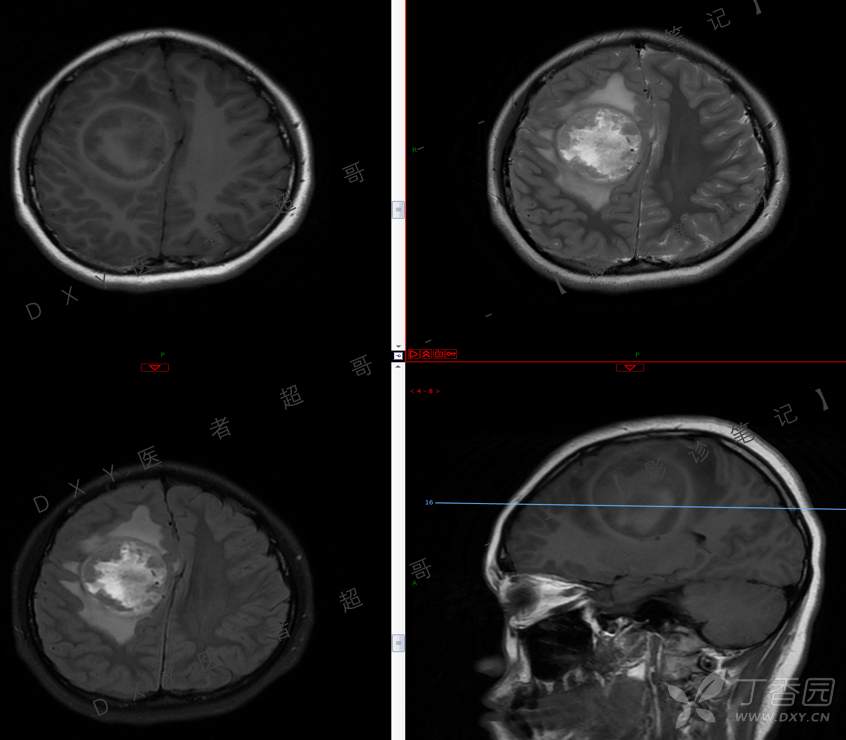

15岁少年,头痛10天,加重伴恶心、呕吐2天,究竟为何?回帖即可查阅病理。

主 诉:头痛10天,加重伴恶心、呕吐2天。

现病史:患者10天前无明显诱因出现头痛,间断发作,无恶心、呕吐,无肢体抽搐等,于当地医院就诊,体温37.4度,予以对症治疗,具体不详,后症状缓解,2天前患者上述症状较前加重,并感双眼胀痛及视物模糊,伴恶心、呕吐,呕吐数次,为胃内容物,再次于当地医院就诊,行颅脑CT考虑“右侧额顶叶病变”,现为求进一步治疗来我院急诊就诊,以“脑脓肿?”收入我科。患者病来精神差,饮食、睡眠欠佳,体重无明显变化。